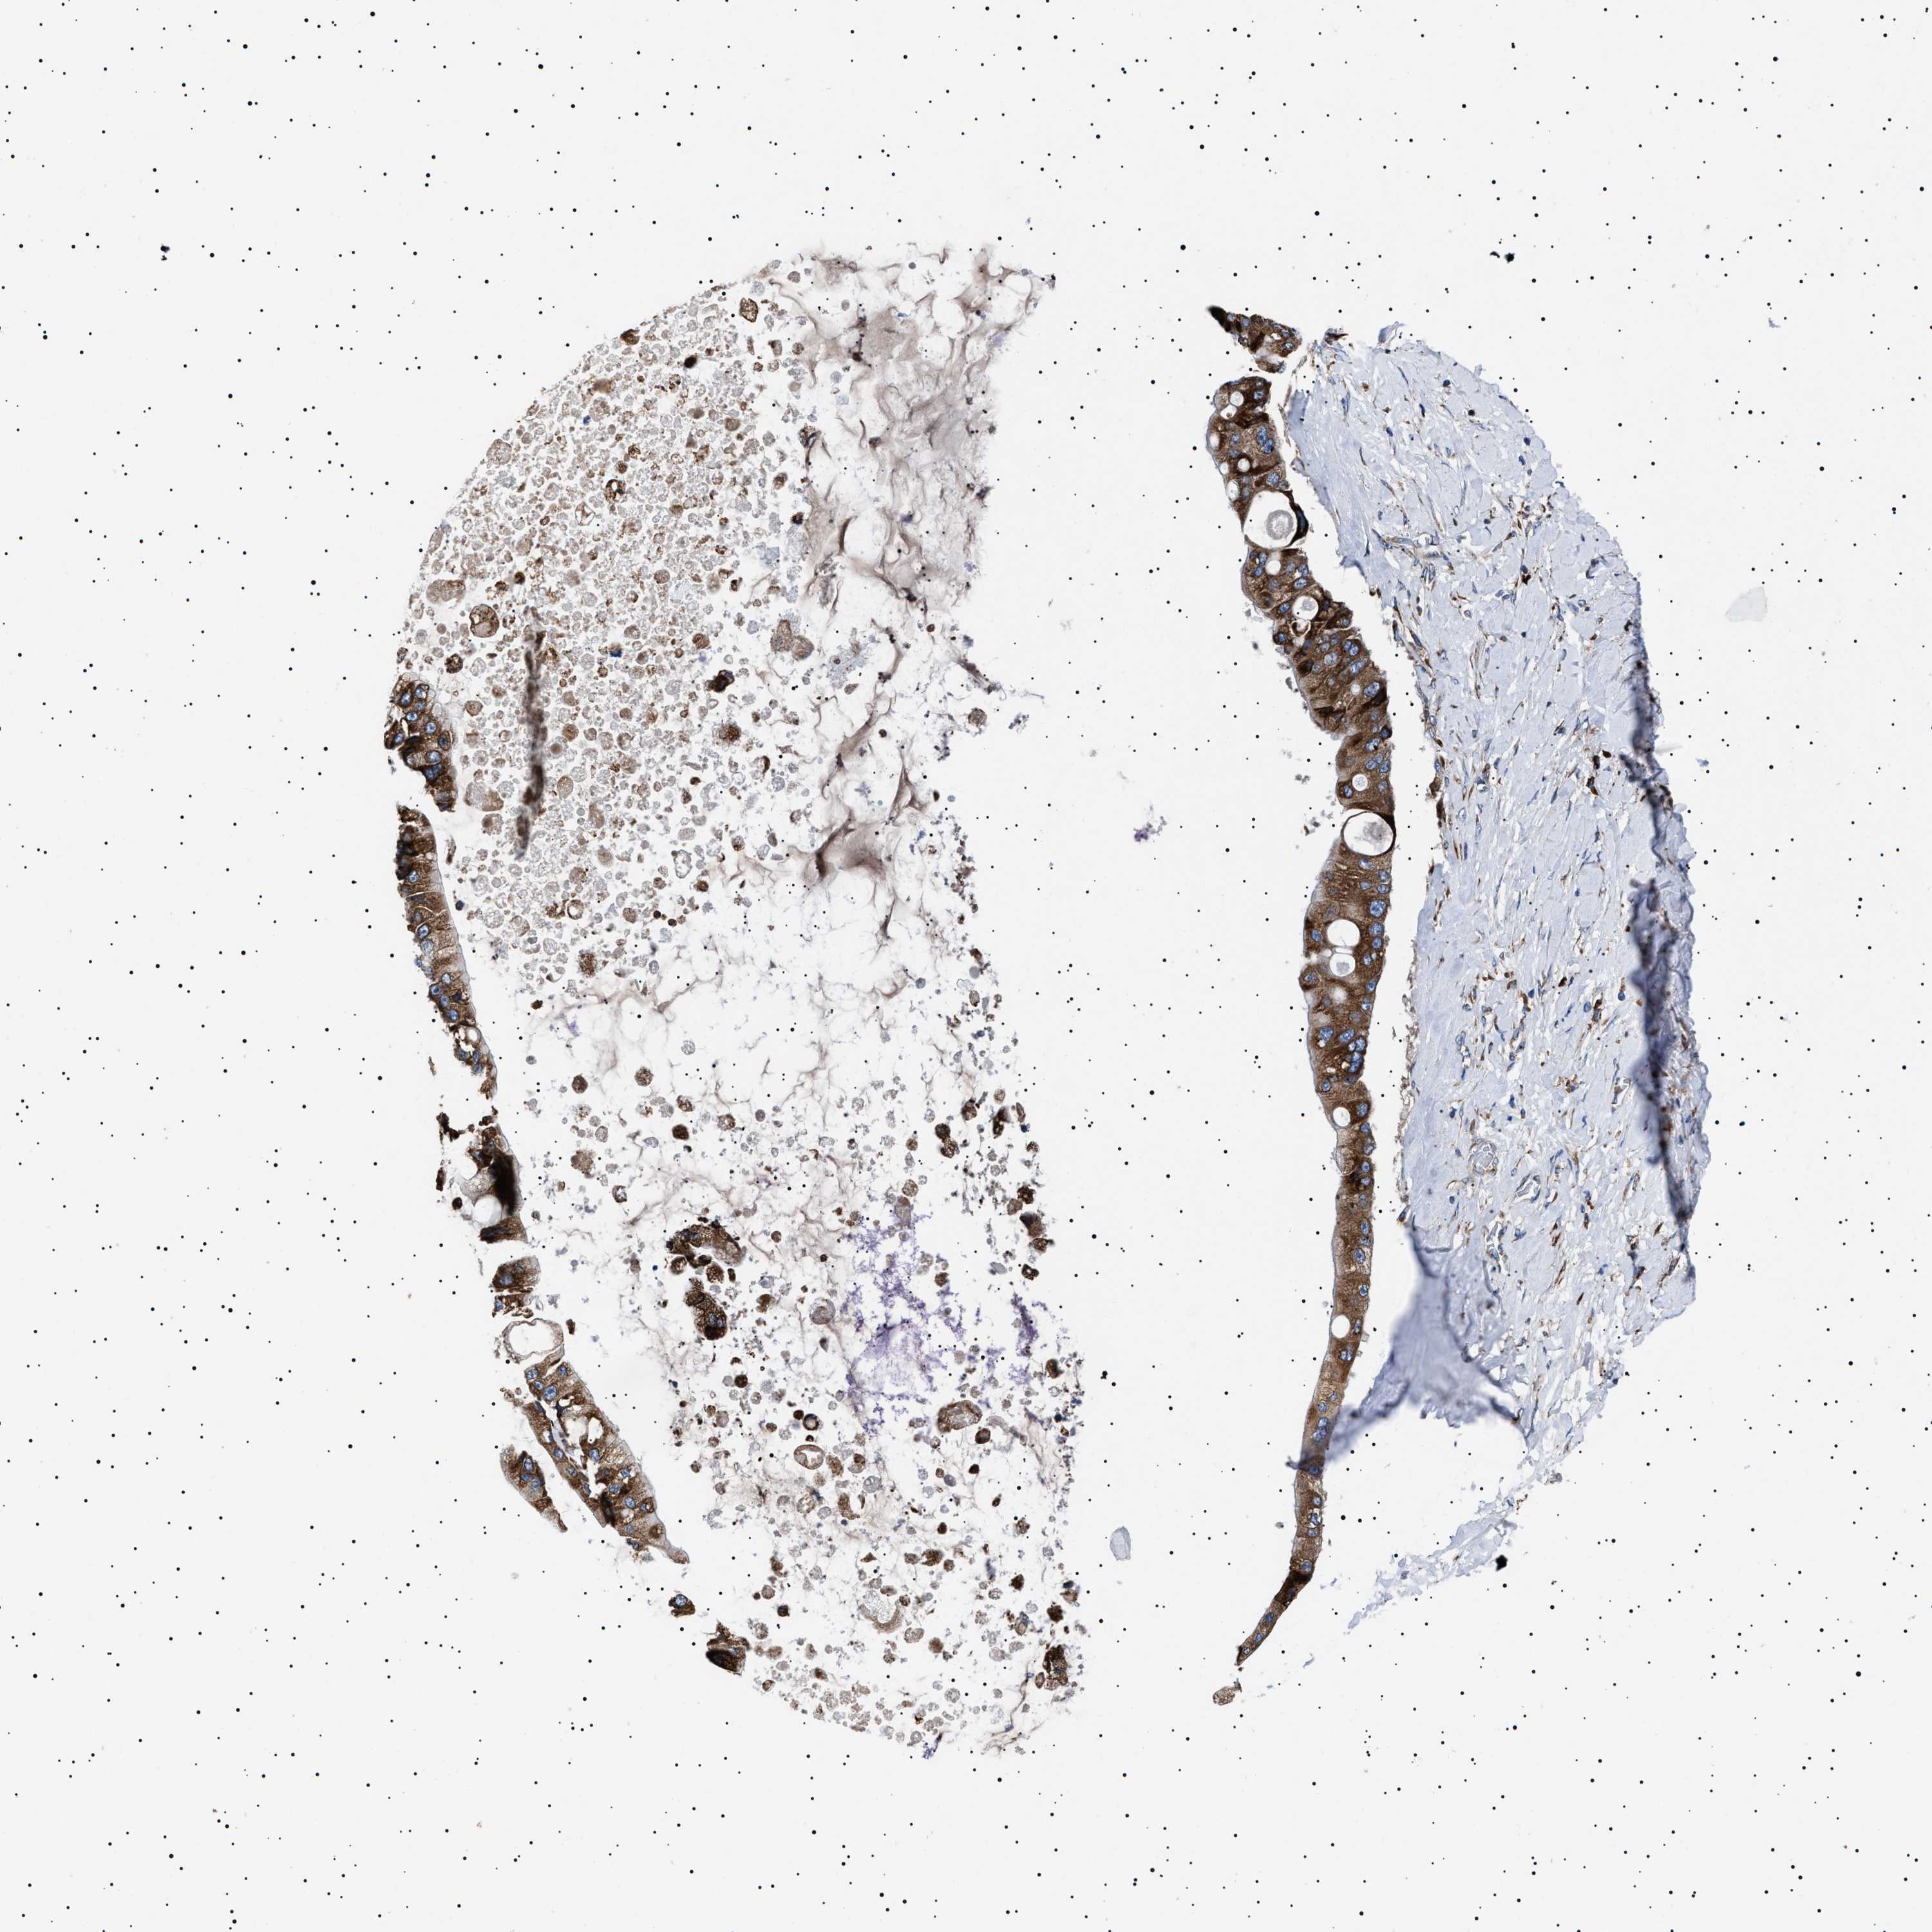

LIVER CANCER - Protein expressioni

A mouse-over function shows sample information and annotation data. Click on an image to view it in a full screen mode. Samples can be filtered based on level of antibody staining by selecting one or several of the following categories: high, medium, low and not detected. The assay and annotation is described here.

Note that samples used for immunohistochemistry by the Human Protein Atlas do not correspond to samples in the TCGA dataset.

Antibody stainingi

Antibody staining in the annotated cell types in the current human tissue is reported as not detected, low, medium, or high, based on conventional immunohistochemistry profiling in selected tissues. This score is based on the combination of the staining intensity and fraction of stained cells.

Each image is clickable and will lead to virtual microscopy that enables deeper exploration of all samples and also displays staining intensity scores, fraction scores and subcellular localization as well as patient and tissue information for each sample.

Antibody HPA001915

Antibody HPA021542

Staining

High

Medium

Low

Not detected

Intensity

Strong

Moderate

Weak

Negative

Quantity

>75%

75%-25%

<25%

None

Location

Nuclear

Cytoplasmic/membranous

Cytoplasmic/membranous,nuclear

Cholangiocarcinoma

Carcinoma, Hepatocellular, NOS